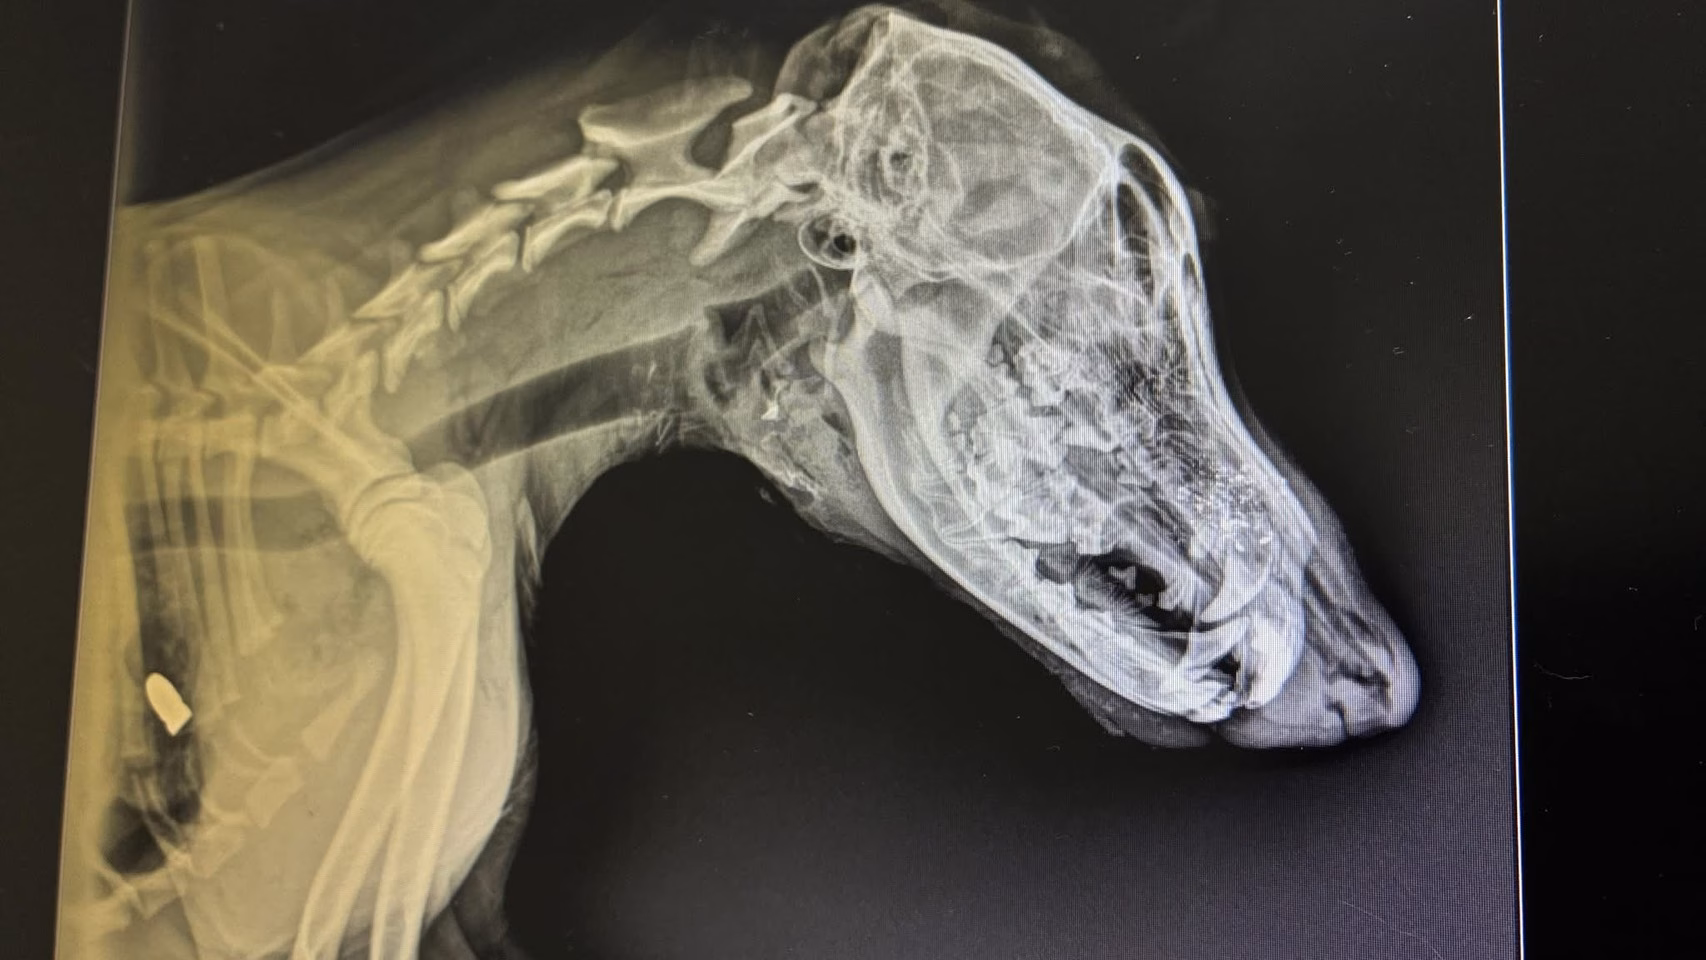

ผลการตรวจเอกซเรย์ของสัตวแพทย์ พบลูกกระสุนฝังอยู่บริเวณรักแร้ใต้ขาหน้าด้านขวา โดยวิถีกระสุนพุ่งจากด้านหน้า ทะลุผ่านลิ้น ลำคอ และไปฝังบริเวณซี่โครงด้านขวา สร้างความเสียหายอย่างรุนแรงต่อร่างกาย